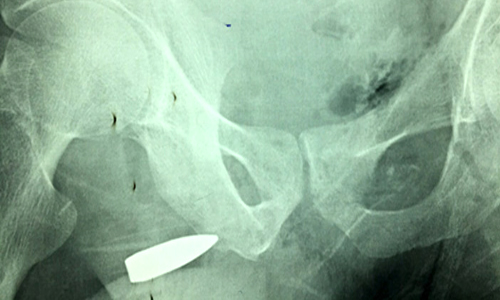

نجح فريق طبي بمستشفى صبيا العام في استخراج طلقة نارية من حوض ثلاثيني تعرض لطلقة نارية، تسببت في اختراق الورك الأيسر، ومن ثم استقرت في منطقة الحوض.

وأوضح رئيس الفريق الطبي الدكتور حسين القاصر، استشاري جراحة عامة أنه فور وصول المريض لقسم الطوارئ بالمستشفى تم الكشف عليه وإجراء الفحوصات الأولية والتصوير التلفزيوني والأشعة المقطعية, تبين أن الطلقة النارية الذي تعرض لها المريض تسببت في كسر الورك الأيسر، ومن ثم استقرت في الحوض، ما استدعى لتدخل جراحي من قبل الفريق الطبي المكون من الدكتور عواجي النعمي، والدكتور حازم خطاب.وبين أنه أجريت للمريض عملية جراحية استغرقت ثلاث ساعات، وتم استخرج الطلقة النارية التي كانت مستقرة في إحدى المناطق التشريحية الصعبة داخل الحوض، وذلك لوجود الأوعية الدموية الرئيسة المغذية للحوض والأطراف السفلية, إلا أن الفريق الطبي تمكن - ولله الحمد - من استخراج الطلقة النارية دون أن تتسبب بأي نزيف أو مضاعفات للمريض, وتم متابعة المريض بعد إجراء العملية، وكذلك التأكد من استقرار حالة المريض الصحية.